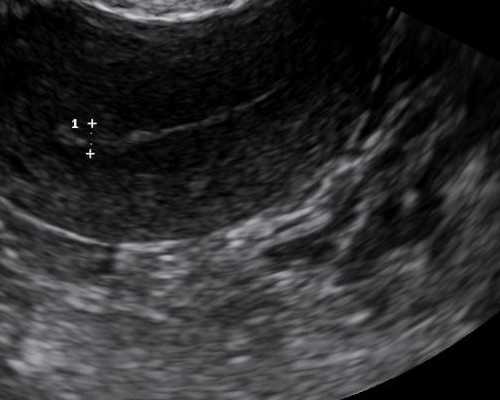

在整个试管婴儿取卵的过程当中,是在B超的监测之下,用一根比较细的取卵针,把所有的卵泡全部给刺破,然后把卵子提取出来。整个过程或多或少算得上是一个小的手术,为了减少大多数女性不舒服的感觉,会在麻醉状态下对女性进行这项手术,因此如果要选择取卵的话,打麻醉药是一种必须的过程。

取卵时,会通过阴超观察取卵位置。当你开始抽卵时,会有一点肿胀和疼痛。此时,建议女性保持呼气和吸气,以创造一种放松的感觉。一般来说,只要你不紧张,整个过程就不像你想象的那么可怕。